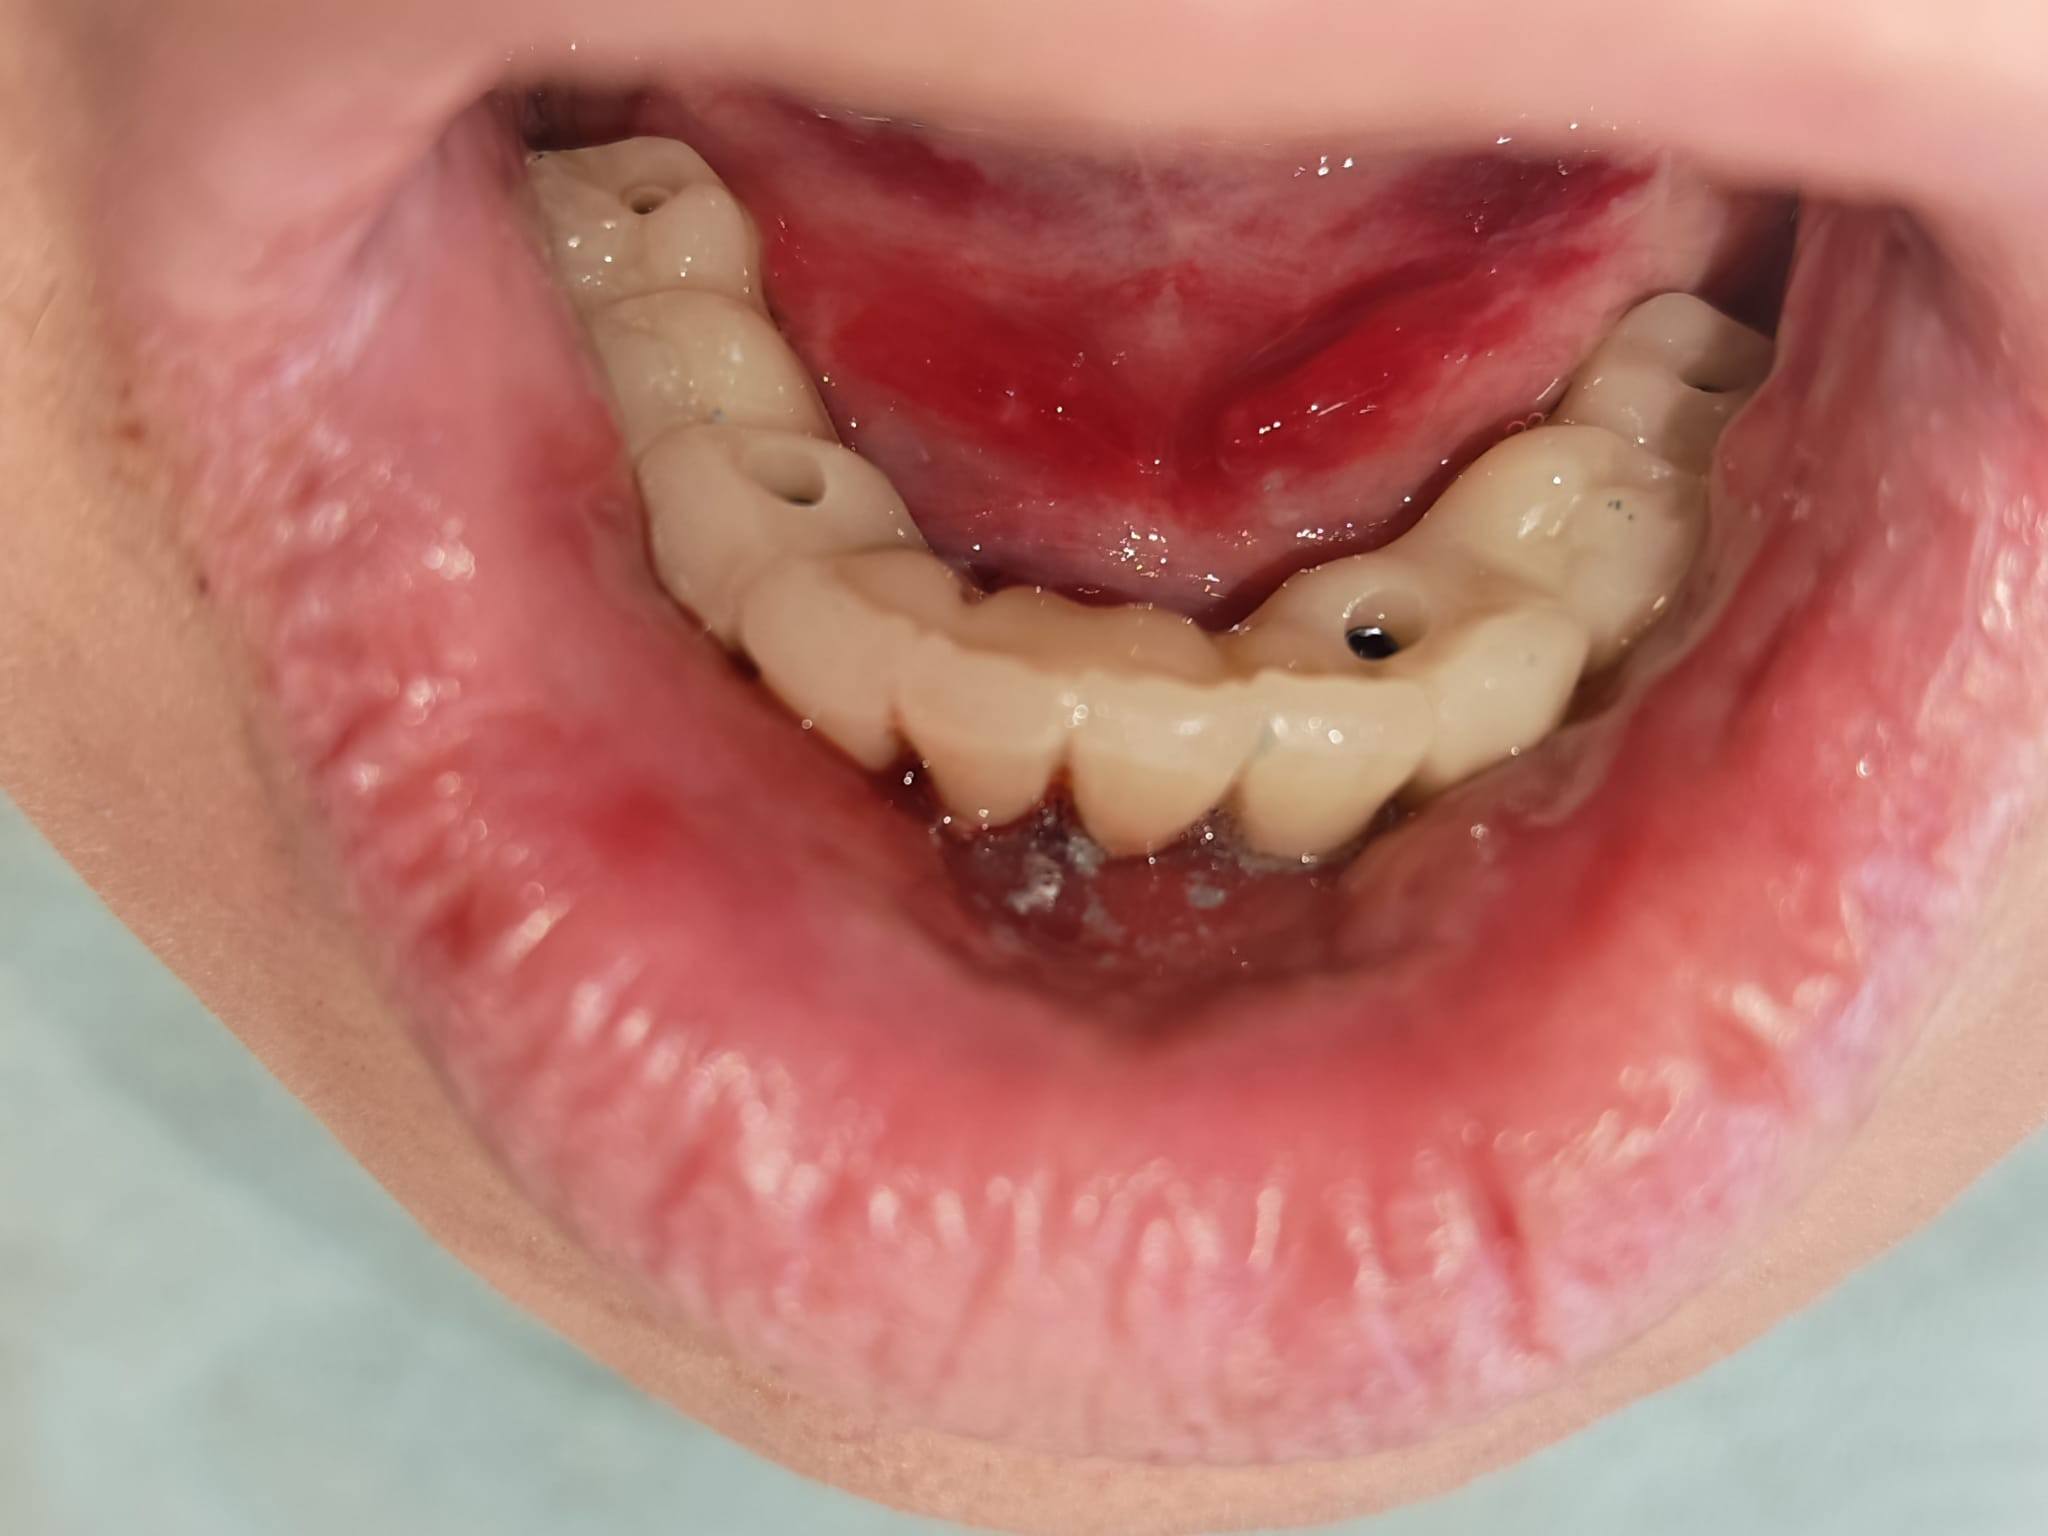

Pacientul s-a prezentat cu o situație clinică ce necesita o soluție fixă, stabilă și estetică pentru arcada inferioară (mandibulă). Alegerea terapeutică a fost o procedură de tip All-on-X cu încărcare imediată. Acest concept permite pacienților să plece din clinică cu dinți ficși temporari în doar 24 de ore de la intervenție, eliminând disconfortul protezelor mobile tradiționale.

Inserarea Implanturilor și a Multiuniturilor: După poziționarea strategică a implanturilor, au fost montate bonturile de tip Multi-Unit, elementele care fac legătura între implant și viitoarea lucrare protetică.

Scanarea „One Shot”: Utilizând tehnologia Scan Abutment One Shot, echipa a realizat scanarea intraorală a arcadei. Această metodă scurtează timpul petrecut de pacient pe scaun și elimină erorile umane asociate cu amprentarea clasică cu silicon.

Sistemul Scan LogiQ: Elementul diferențiator al acestui caz a fost utilizarea sistemului Scan LogiQ. Acesta a permis obținerea unei pasivități excelente a lucrării. În termeni medicali, pasivitatea înseamnă că lucrarea se adaptează perfect, fără a exercita tensiuni anormale asupra implanturilor sau osului înconjurător, asigurând longevitatea tratamentului.